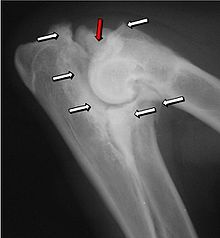

Ununited anconeal process

Most primary lesions are related to osteochondrosis, a disease of the joint cartilage, and osteochondritis dissecans (OCD), the separation of a flap of cartilage on the joint surface. Other common causes of elbow dysplasia include an ununited anconeal process (UAP) and fragmented or ununited medial coronoid process (FCP or FMCP).[1]

UAP is caused by a separation from the ulna of the ossification center of the anconeal process.[7] FMCP is caused by a failure of the coronoid process to unite with the ulna.